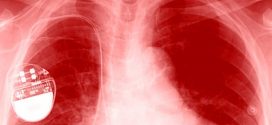

FDA: Pacemakers vulnerable to hacks

The US Food and Drug Administration announced today that 465,000 pacemakers have a security vulnerability that could be exploited to make the device operate too quickly or deplete its batteries, and these devices need firmware updates to keep them from getting hacked. “Many medical devices – including St. Jude Medical’s implantable cardiac pacemakers – contain configurable embedded computer systems that …